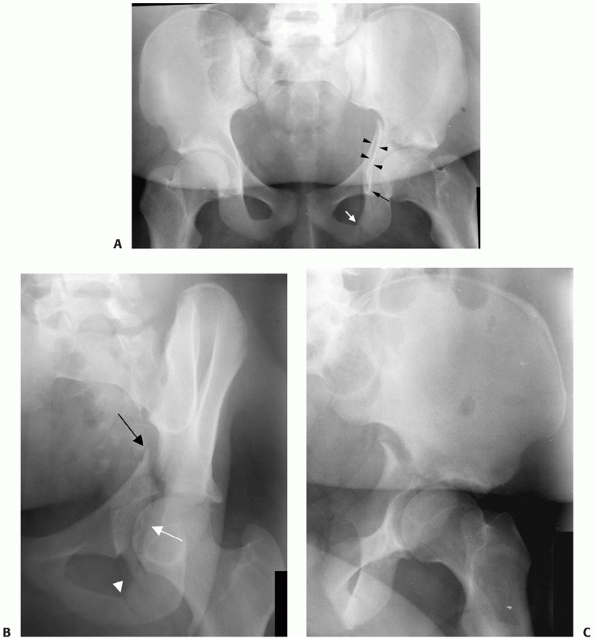

FIGURE 45-23 Radiographic appearance of the transverse fracture. A.

They are the only elementary fracture pattern that breaks both the

anterior and posterior border of the innominate bone. The fracture

separates the innominate bone into two pieces: the upper iliac piece

and the lower ischiopubic segment. The upper fragment is intact to the

ilium, while the ischiopubic fragment rotates about the symphysis

pubis. This results in a medial and superior displacement of the head,

as it follows the ischiopubic segment. This rotation also typically

produces a greater translational displacement of the transverse

fracture at the posterior border rather than the anterior border of the

bone. Transverse fractures are subdivided by where the fracture crosses

the articular surface. Transtectal fractures cross the weight-bearing

dome of the acetabulum. Juxtatectal fractures cross the articular

surface at the level of the top of the cotyloid fossa. Infratectal

fractures cross the cotyloid fossa (Fig. 45-22).

As the location of the fracture moves more superior on the articular

surface, the orientation of the fracture also becomes more vertical and

the size of the intact remaining articular surface decreases. This has

definite implications for the surgical treatment of these injuries. The

AP radiograph demonstrates a disruption of both the ilioischial and

iliopectineal lines as well as the anterior and posterior rim shadows.

In transtectal fractures, the roof line will be disrupted as well.

However, the ilioischial line maintains its normal relationship with

the radiographic U, as there is no fracture at this level. The oblique

views will show disruption of the pelvic brim as well as the posterior

border of the bone. The ischial ramus will not be fractured. On CT

scan, the fracture line is oriented in an AP direction in the axial

section (Fig. 45-23).